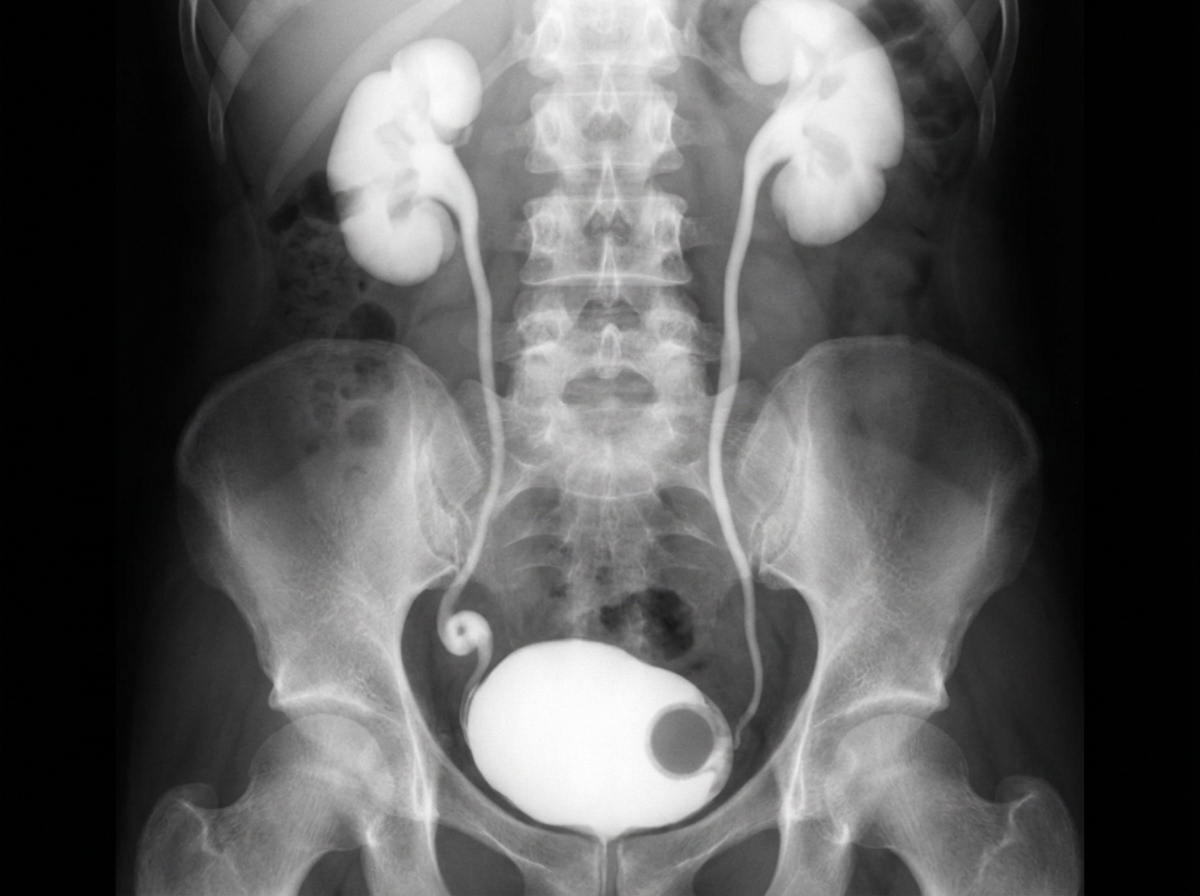

A 10-year-old girl was evaluated for recurrent UTI and dysuria. An IVP finding is shown. What is the preferred treatment option for this case?

Explanation: ***Endoscopic incision*** - **Endoscopic incision** is the preferred first-line treatment for **ureterocele** (cobra head sign on IVP) in children, offering minimal invasivity with excellent success rates. - It provides immediate drainage relief and preserves **renal function** while avoiding major surgical complications in pediatric patients. *Nephrectomy with pyeloureterectomy* - This is an **extreme surgical approach** reserved for cases with **non-functioning kidneys** or severe complications, not as first-line treatment. - **Unnecessary loss of renal tissue** in a child when simpler endoscopic options can effectively treat the ureterocele. *STING operation* - **Subureteral injection** is used for **vesicoureteral reflux** treatment, not for ureterocele management. - Does not address the **anatomical obstruction** caused by the ureterocele that requires decompression. *Lich-Gregoir technique* - This **ureteroneocystostomy** technique is used for **ureteral reimplantation** in cases of reflux or ureteral strictures. - **Not indicated** for ureterocele treatment where endoscopic decompression is the preferred initial approach.